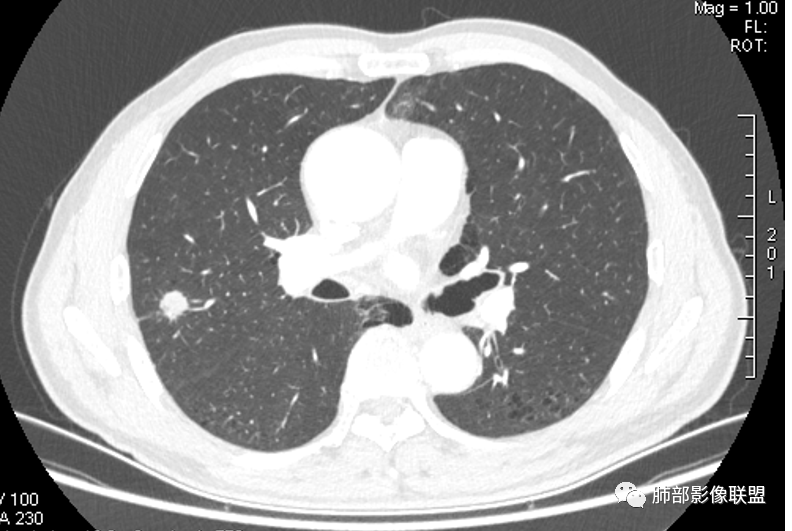

晨读:双肺胸膜下多发小气囊,大小不一,右肺结节,内部可见小空洞,洞壁光滑,厚薄不一,偏心性生长,近段血管束增粗,有分叶,毛刺(软),有晕征,平扫密度尚可,增强后不均匀强化,可见低密度坏死,及部分血管穿行,体检发现,考虑恶性:腺癌,鉴别炎性结节

右上叶结节,轻分叶,结节有长短不一毛刺,结节周围GGO边界清,有血管集束征,肺窗结节周围似可见卫星灶,可见鬼脸征,良恶性征象都有,但GGO边界清,浸润性腺癌耍考虑,临床症状轻微,体捡发现,似可见卫星灶和鬼脸征,炎性肉芽肿TB或隐球菌要鉴别。

我们从外朝内,肺气肿背景

虽然良恶性征象都有,但是这个病灶增强后坏死比较明显,如果是恶性:腺癌这样大小的结节坏死很少见,只有低分化腺癌可以坏死,但是低分化腺癌这种大小一般会有周围转移表现(叶间胸膜结节,癌淋或者淋巴结明显肿大),如果是鳞癌,收缩力,坏死情况以及没有支气管截断都不太支持,而且结节远端有几个小结节样改变,大家可能认为是血管,但我觉得应该是卫星灶。所以觉得隐球可能较大。壁胸膜的牵拉线也没有引起胸膜凹陷,比较纤细,至于病理中的丝状物不一定是真菌菌丝。

6.灶周见小结节影(卫星灶),边界不甚清晰。